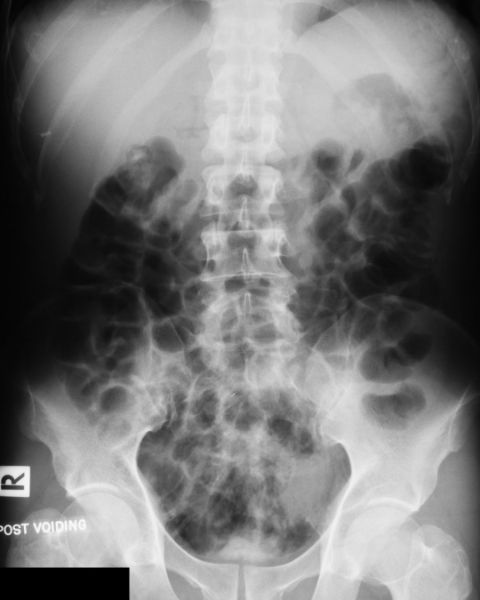

İVP, yani İntravenöz Piyelografi, böbreklerin, idrar yollarının ve üreterlerin (böbrekten mesaneye idrar taşıyan kanallar) görüntülenmesini sağlayan radyolojik bir tetkiktir. İşlem, damar yolundan verilen kontrast madde ile yapılır.

Kısaca, İVP, idrar yollarını görmek için intravenöz kontrast kullanılarak yapılan özel bir röntgen tetkikidir.